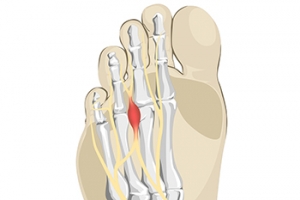

A tailor’s bunion, also known as a bunionette, occurs when the 5th metatarsal bone (the bottom bone on the little toe) begins to shift outwards. Tailor’s bunions are very similar to a normal bunion which occurs on the big toe, but instead, they occur on the pinky toe. A tailor’s bunion will present itself as a swollen bump on the outside of the pinky toe, and it may get larger over time. They can be red and painful, and they tend to get worse as they rub against the shoe. Some of the reasons Tailor’s bunions may form include shoes that don’t fit correctly, an inherited structural foot problem, loose ligaments in the foot, or an inverted foot that leans outwards. Patients who are struggling with a painful Tailor’s bunion should consult with a podiatrist for suggestions on both relieving the pain and treating the bunion.

A tailor’s bunion, also known as a bunionette, occurs when the 5th metatarsal bone (the bottom bone on the little toe) begins to shift outwards. Tailor’s bunions are very similar to a normal bunion which occurs on the big toe, but instead, they occur on the pinky toe. A tailor’s bunion will present itself as a swollen bump on the outside of the pinky toe, and it may get larger over time. They can be red and painful, and they tend to get worse as they rub against the shoe. Some of the reasons Tailor’s bunions may form include shoes that don’t fit correctly, an inherited structural foot problem, loose ligaments in the foot, or an inverted foot that leans outwards. Patients who are struggling with a painful Tailor’s bunion should consult with a podiatrist for suggestions on both relieving the pain and treating the bunion.